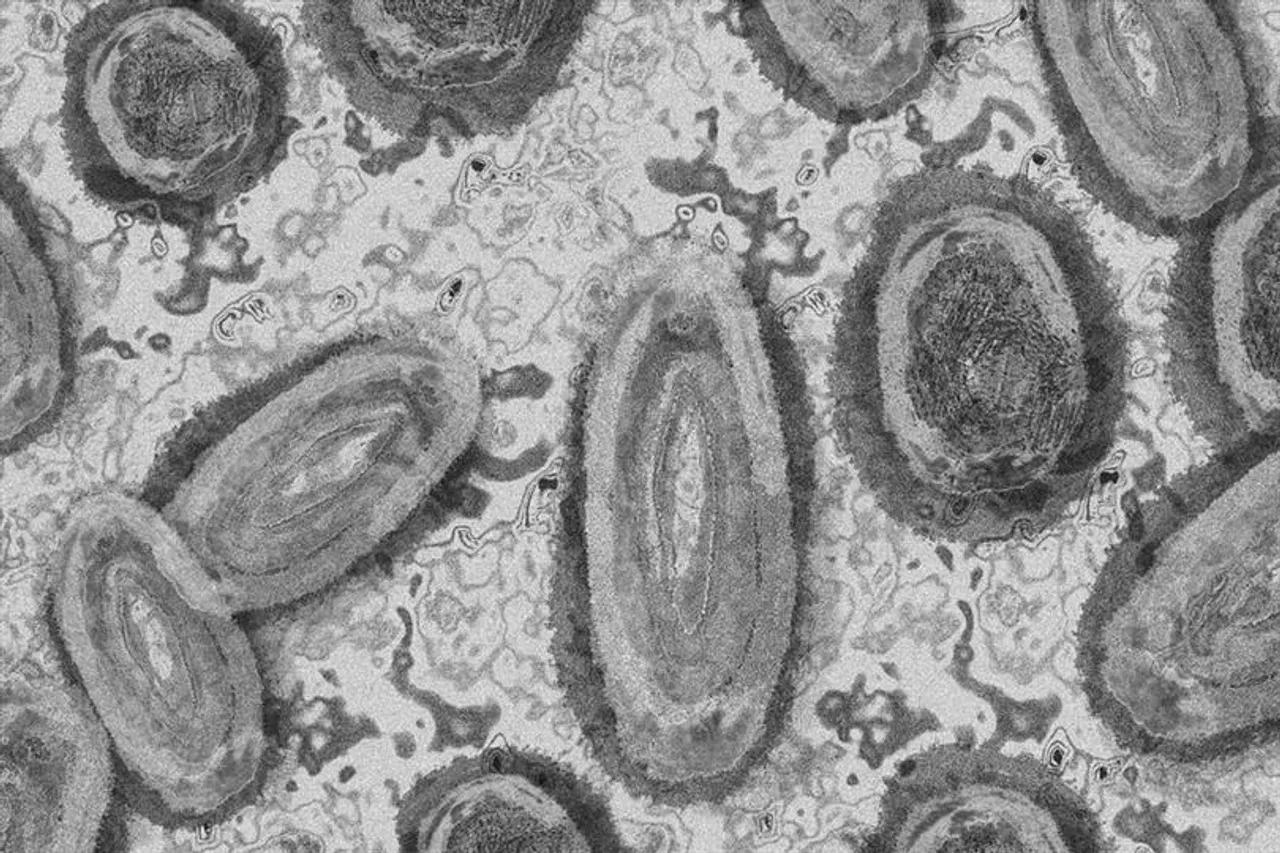

নিজস্ব সংবাদদাতা : সংযুক্ত আরব আমিরাত ফেরত এক ব্যক্তিকে মাঙ্কিপক্স সন্দেহে কেরালেরর একটি হাসপাতালে ভর্তি করা হল। ব্যক্তির শরীরে যে লক্ষযণগুলি রয়েছে তা মাঙ্কি পক্সের উপসর্গ বলেই জানা যাচ্ছে।রাজ্যের স্বাস্থ্যমন্ত্রী বীনা জর্জ জানিয়েছেন, ব্যক্তির নমুনা সংগ্রহ করে পরীক্ষার জন্য জাতীয় ভাইরোলজি ইনস্টিটিউটে পাঠানো হয়েছে।

পরীক্ষার রিপোর্ট পাওয়ার পরই নিশ্চিত হওয়া যাবে।বিদেশে একজন মাঙ্কিপক্স রোগীর সাথে ঘনিষ্ঠ যোগাযোগ করেছিলেন ওই ব্যক্তি। ফলে বাড়ছে আতঙ্ক।